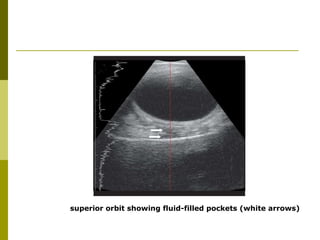

superior orbit showing fluid-filled pockets (white arrows)

superior orbit showingfluid-filled pockets (white arrows)